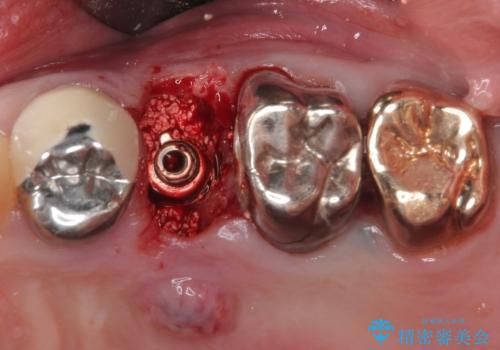

破折した奥歯 抜歯即時埋入インプラントによる補綴治療

目視で歯根が破折していることが分かり、保存不可能と判断されたたため、抜歯即時埋入インプラントによる補綴治療を行うこととしました。

抜歯即時埋入後にはずっと気になっていた排膿が消え、痛みも腫れも特になく、3ヶ月という短期間で無事に治療を終えることができました。